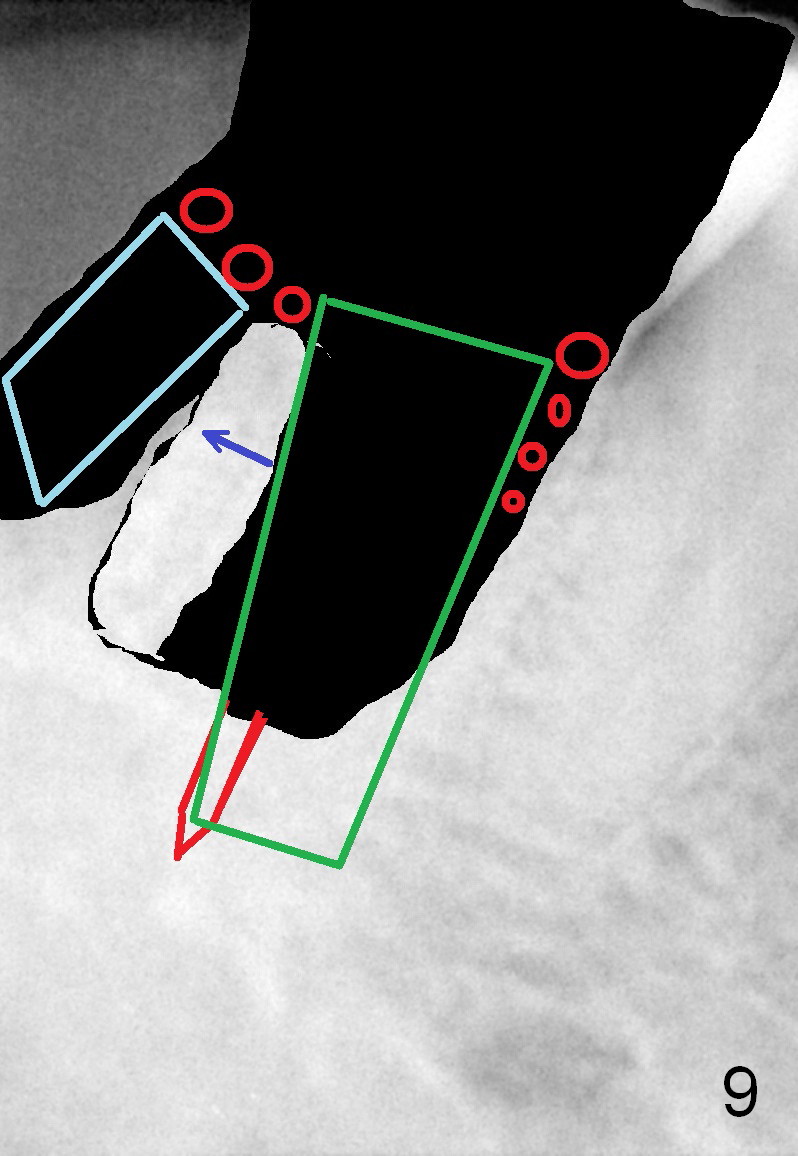

Fig.6 is an illustration after extraction (S: septum; M: mesial socket). Osteotomy is initiated with a pilot drill in the distal aspect of the mesial socket or the mesial aspect of the septum (Fig.7). The osteotomy is enlarged with osteotomes; at the same time the septum is being pushed distally (Fig.8 blue arrow) with leaning the osteotomes distally (white arrow). When an implant is placed, the apex is mainly seated in the mesial socket, while the coronal end is more or less inclined distally for restoration. The apical half of the distal sockets is packed with collagen plug or dressing, whereas the remaining sockets and coronal exposed threads are filled with bone graft (Fig.9,10 red circles). An incision is made if needed for better visibility. The most coronal socket is going to be obliterated by a cemented or healing abutment. Does the treatment planning help surgery?